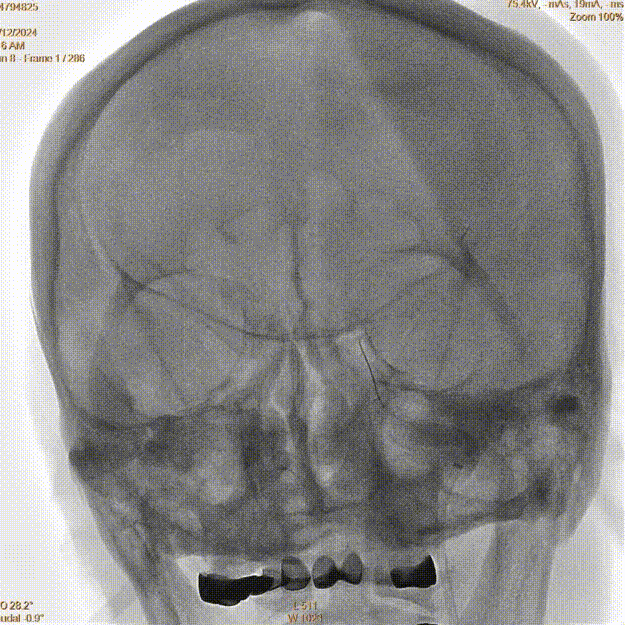

入院时CT:ASPECTS 10分。